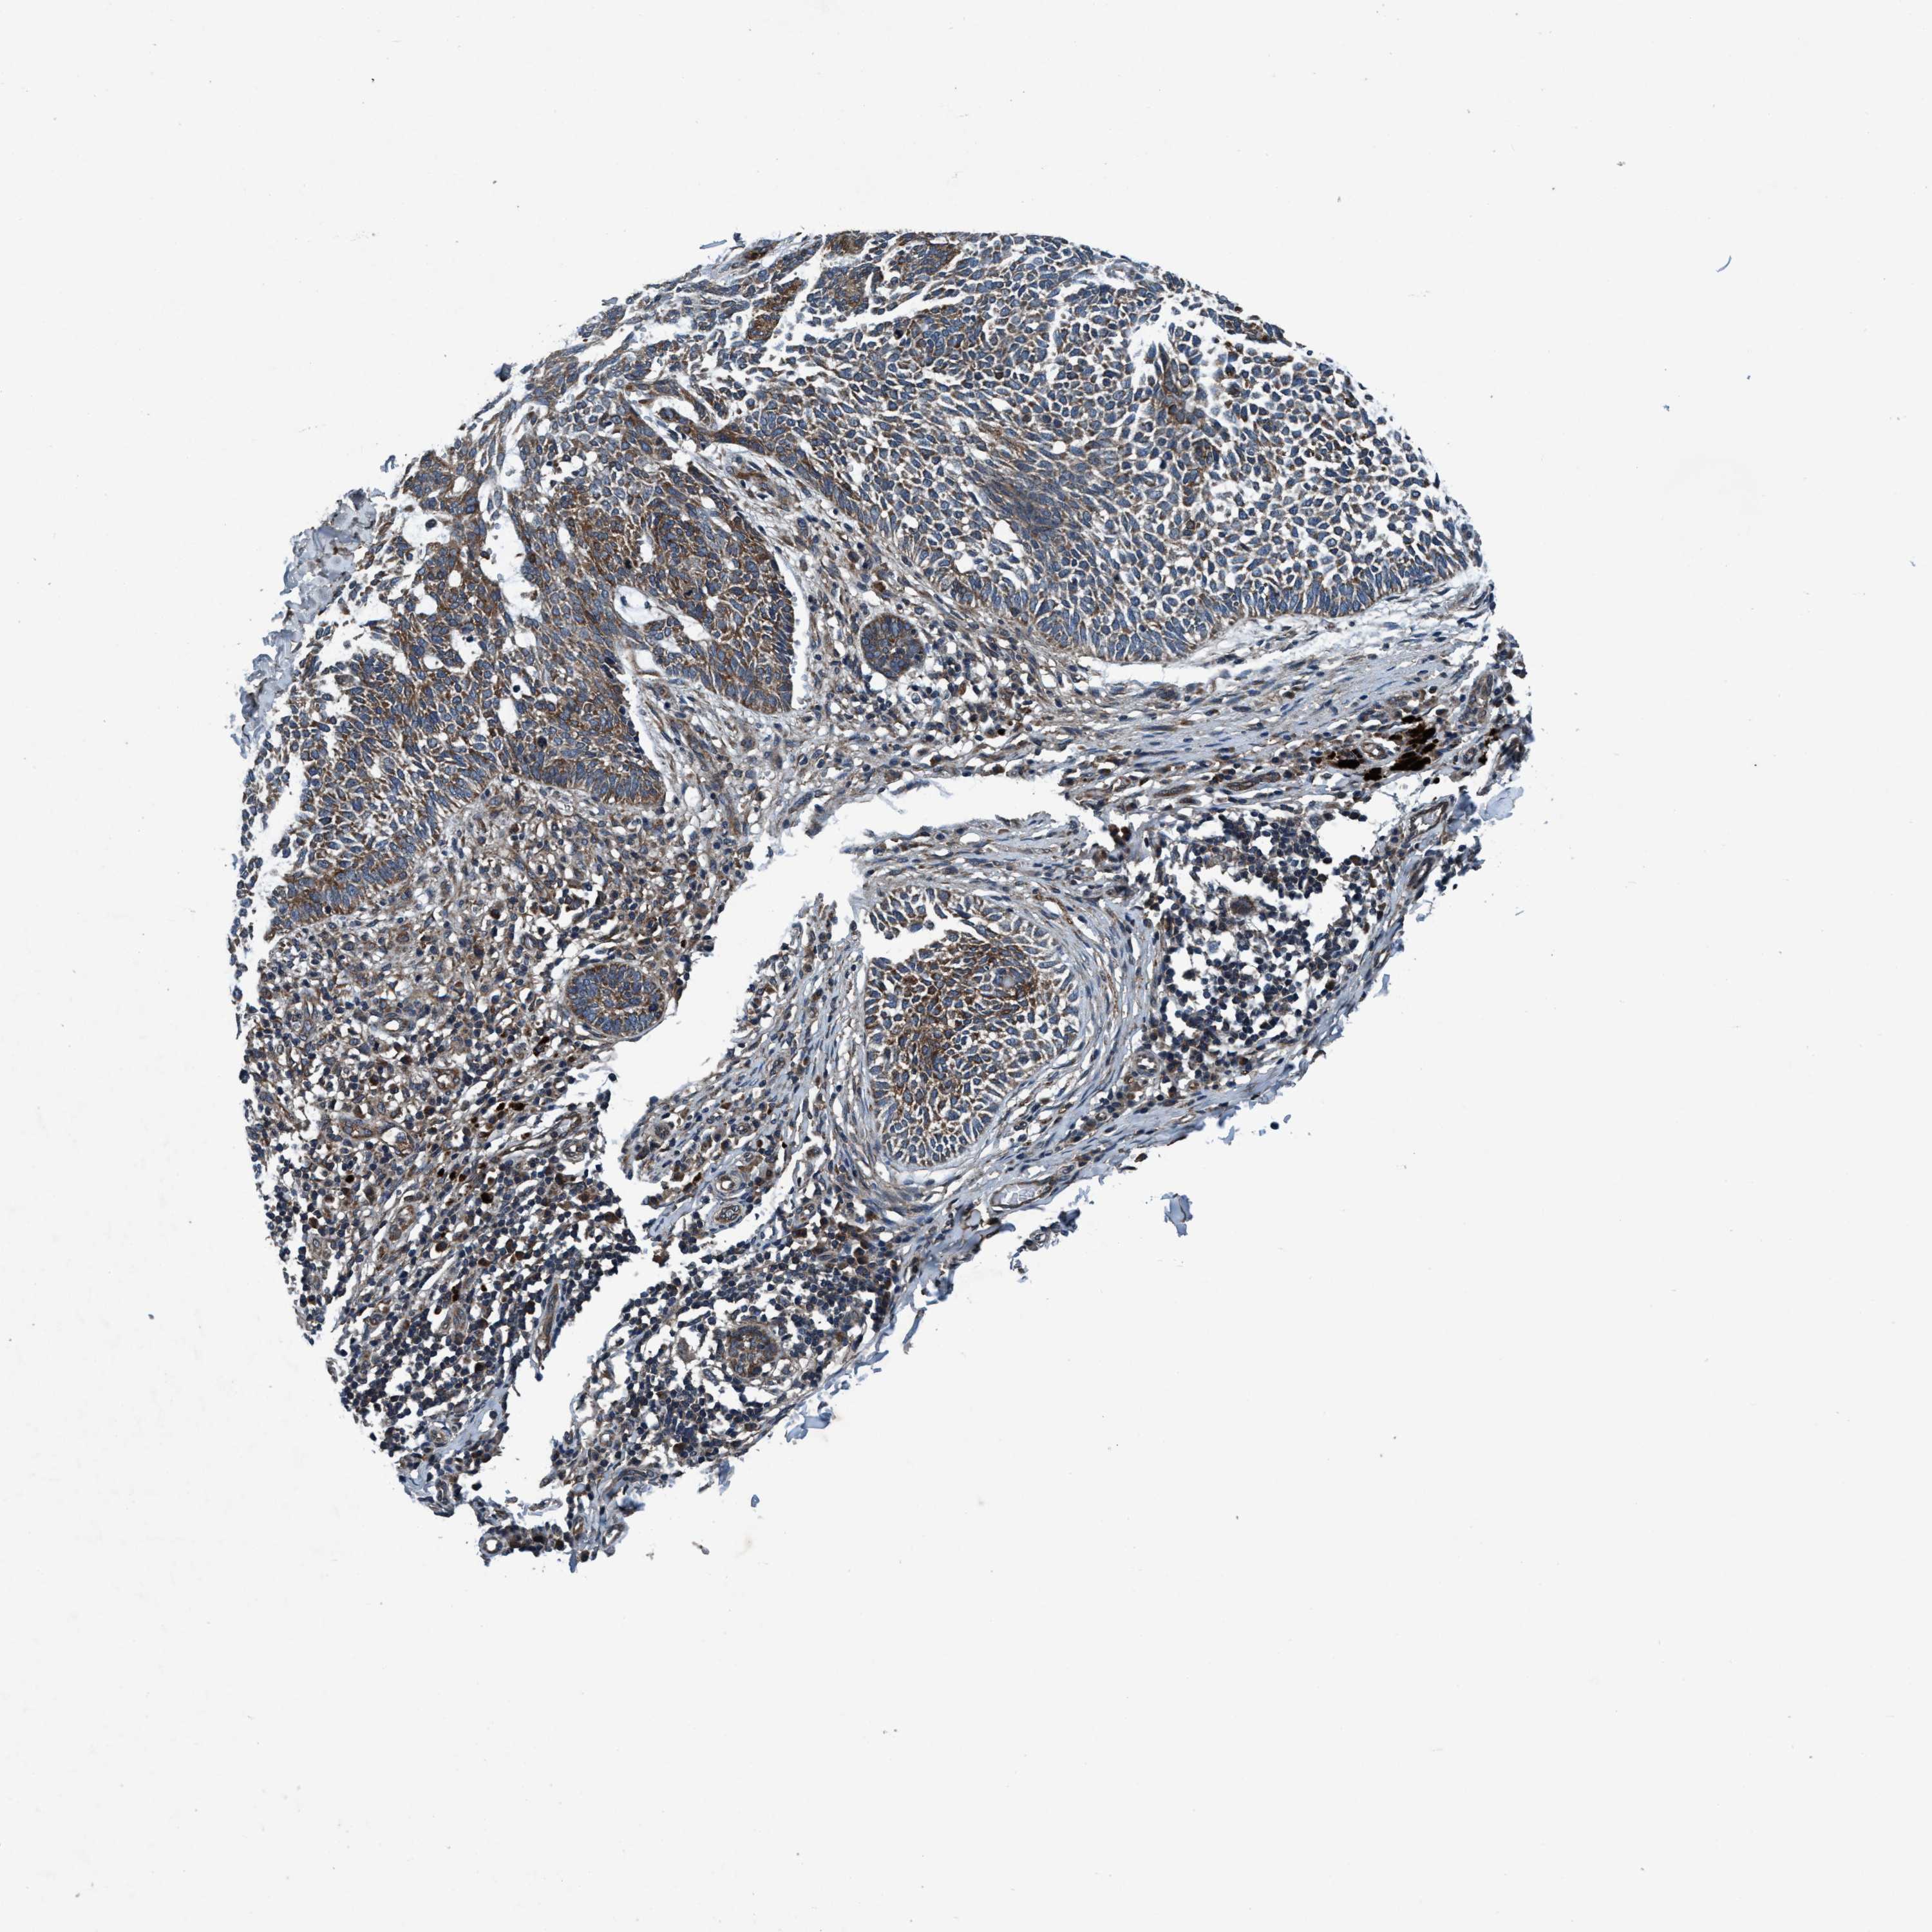

CANCER SKIN CANCER Show tissue menu

Basal cell and squamous cell cancer

SKIN CANCER - Protein expressioni

A mouse-over function shows sample information and annotation data. Click on an image to view it in a full screen mode. Samples can be filtered based on level of antibody staining by selecting one or several of the following categories: high, medium, low and not detected. The assay and annotation is described here.

Each image is clickable and will lead to virtual microscopy that enables deeper exploration of all samples and also displays staining intensity scores, fraction scores and subcellular localization as well as patient and tissue information for each sample.

Antibody HPA064427

Antibody HPA075510

Antibody CAB021903

Staining

High

Medium

Low

Not detected

Intensity

Strong

Moderate

Weak

Negative

Quantity

>75%

75%-25%

<25%

None

Location

Nuclear

Cytoplasmic/membranous

Cytoplasmic/membranous,nuclear

Basal cell carcinoma

BCC, high aggressive

Squamous cell carcinoma, NOS